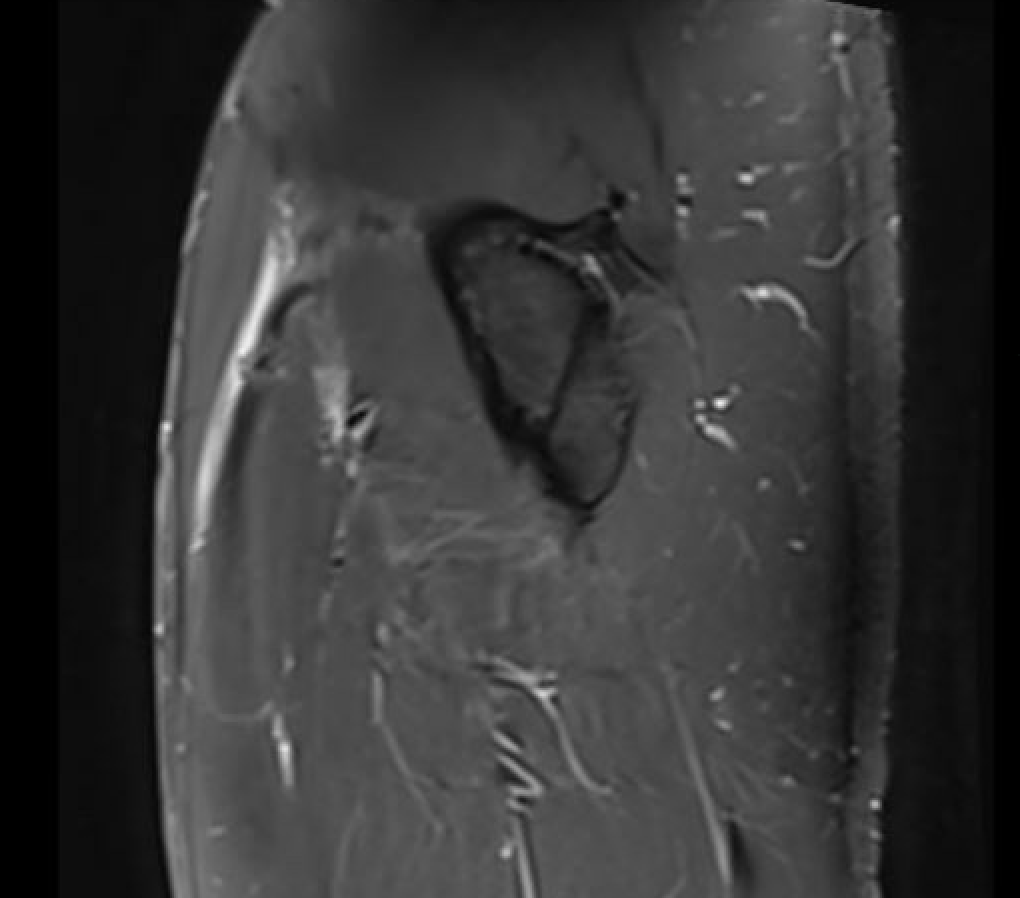

Normal central tendon

Proximal myotendinous / tendon injuries

MRI